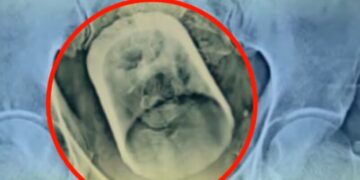

Ο επικεφαλής χειρουργός, Μακχντουλούλ Χακ, περιέγραψε πώς ξεκίνησε η διάγνωση. Οι πρώτες ακτινογραφίες και ο υπέρηχος αποκάλυψαν ότι κάτι είχε μπλοκάρει σοβαρά το πεπτικό του σύστημα.

Το σοκ ήρθε όταν οι γιατροί διαπίστωσαν πως το αντικείμενο που προκάλεσε τη δυσλειτουργία ήταν… ένα γυάλινο ποτήρι.